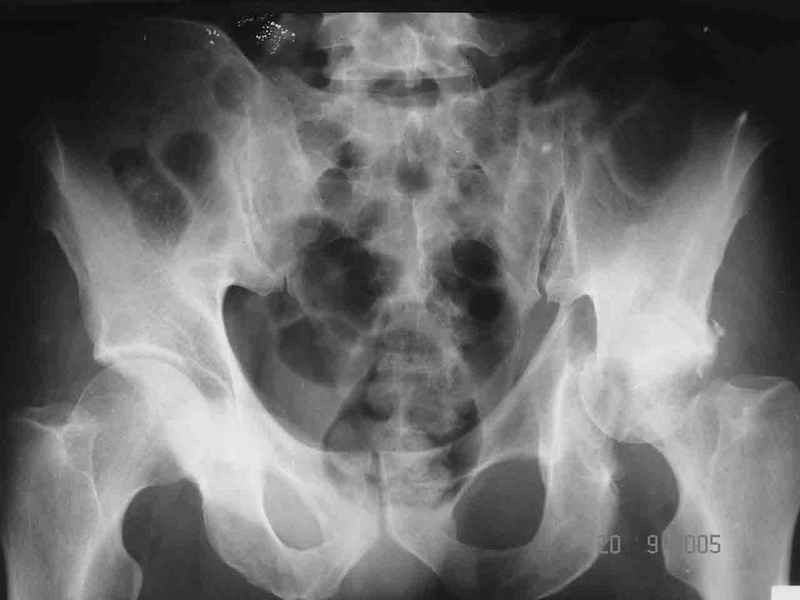

19/05/03

При поступлении в госпиталь 3.06.03

Больной 18 мая 2003 года в автоаварии получил перелом левой вертлужной впадины, вывих бедра. Госпитализирован в один из стационаров области.Вывих вправлен. В последствии бедро вывихивалось еще дважды. На консультацию был представлен снимок от 19.05.03г., больной переведен к нам 3.06.03г. Снимок при поступлении - перелом впадины, задне-верхний вывих бедра. 05.06.2003 г. выполнено открытое вправление вывиха левого бедра и остеосинтез стенки вертлужной впадины двумя винтами. Послеоперационный период без осложнений. Объем движений в левом тазобедренном суставе восстановился полностью. Выписан на амбулаторное лечение в удовлетворительном состоянии с рекомендациями 3 месяца ходить на костылях без нагрузки на оперированную конечность. На контрольных рентгенограммах левого тазобедренного сустава 13.10.2003 г. - признаки консолидации перелома; плотность, форма головки и состояние суставных поверхностей удовлетворительные. Разрешена дозированная осевая нагрузка, на конечность с использованием дополнительной опоры. 19.12.2003 г. больной обратился с жалобами на боли в левом тазобедренном суставе. На рентгенограммах левого тазобедренного сустава 19.12.2003 г., 20.02.04г. - асептичекий некроз головки бедра. 5.04.04г. - эндопротез. Сейчас ходит без трости, не хромает. Особенность эндопротезирования - при удалении винтов прослежена линия перелома заднего края впадины и предложено установить чашку несколько меньшего диаметра, чтобы она была покрыта несломанной частью.